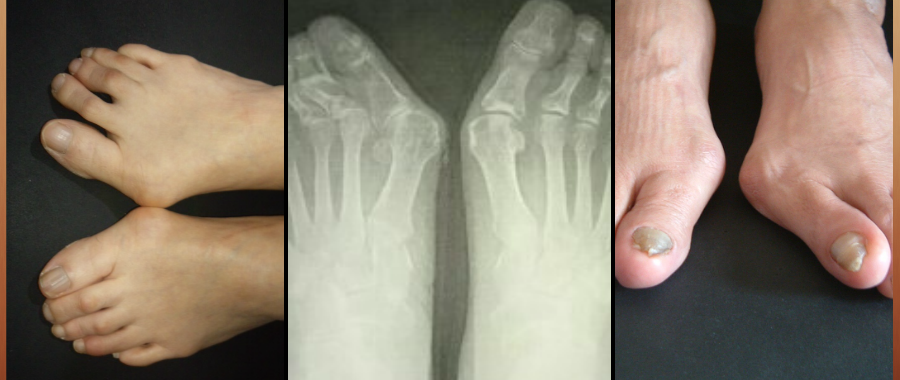

足に不適切な環境が痛みや外反母趾、内反小趾、ハンマートゥなど様々な症状に。

※ 取り戻すことの出来ない変形症状には悪化を防ぎ、痛みに繋がる原因を取り除いた足の環境が大切です。

市販の靴でこのような変形、症状は作られますが、私どもの靴づくりは変形した足、痛みなどに対応し、靴型から作られます。

外反母趾、リウマチ、膠原病、など靴が足に合わない事で足の変形だけでなく、

様々な病気と身体に大きな負担を掛け悩む方は少なくありません。